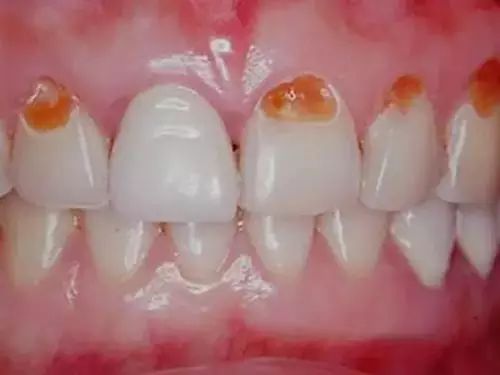

這個是牙齒泡在碳酸飲料裏一年的變化

呢啲唔同種類嘅飲料對牙齒嘅侵蝕指數超級高

因為,大部份飲品嘅PH值喺2.2 - 4.9之間,而牙齒表面嘅琺瑯質溶解臨界PH值係5.5!如果你嗰杯飲品唔離口,就等於係將牙齒浸喺呢種液體度,慢慢溶解!

喺醫學界,呢個情況叫做“酸蝕症”,簡單嚟講就係牙齒長期同酸性物質接觸導致嘅牙齒硬組織溶解失去。